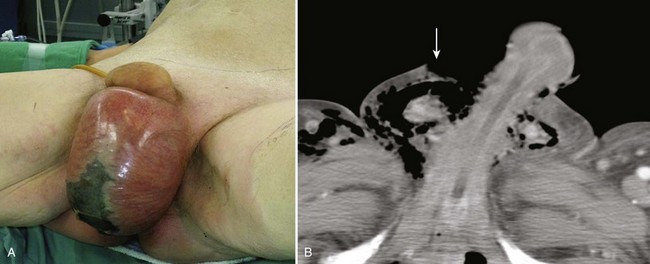

The diagnosis of penile fracture is often straightforward and can be made reliably by history and physical examination. Patients usually describe a cracking or popping sound as the tunica tears, followed by pain, rapid detumescence, and discoloration and swelling of the penile shaft. If the Buck fascia remains intact, the penile hematoma remains contained between the skin and tunica, resulting in a typical eggplant deformity. If the Buck fascia is disrupted, hematoma can extend to the scrotum, perineum, and suprapubic regions (Fig. 88–1 on the Expert Consult website).

The swollen, ecchymotic phallus often deviates to the side opposite the tunical tear because of hematoma and mass effect. The fracture line in the tunica albuginea may be palpable. Because fear and embarrassment are commonly associated, the patient’s presentation to the emergency department or clinic is sometimes significantly delayed.

Figure 88–1 “Eggplant deformity,” the classic appearance of penile fracture sustained during intercourse, with hematoma of the penile shaft and ecchymosis extending into the scrotum.